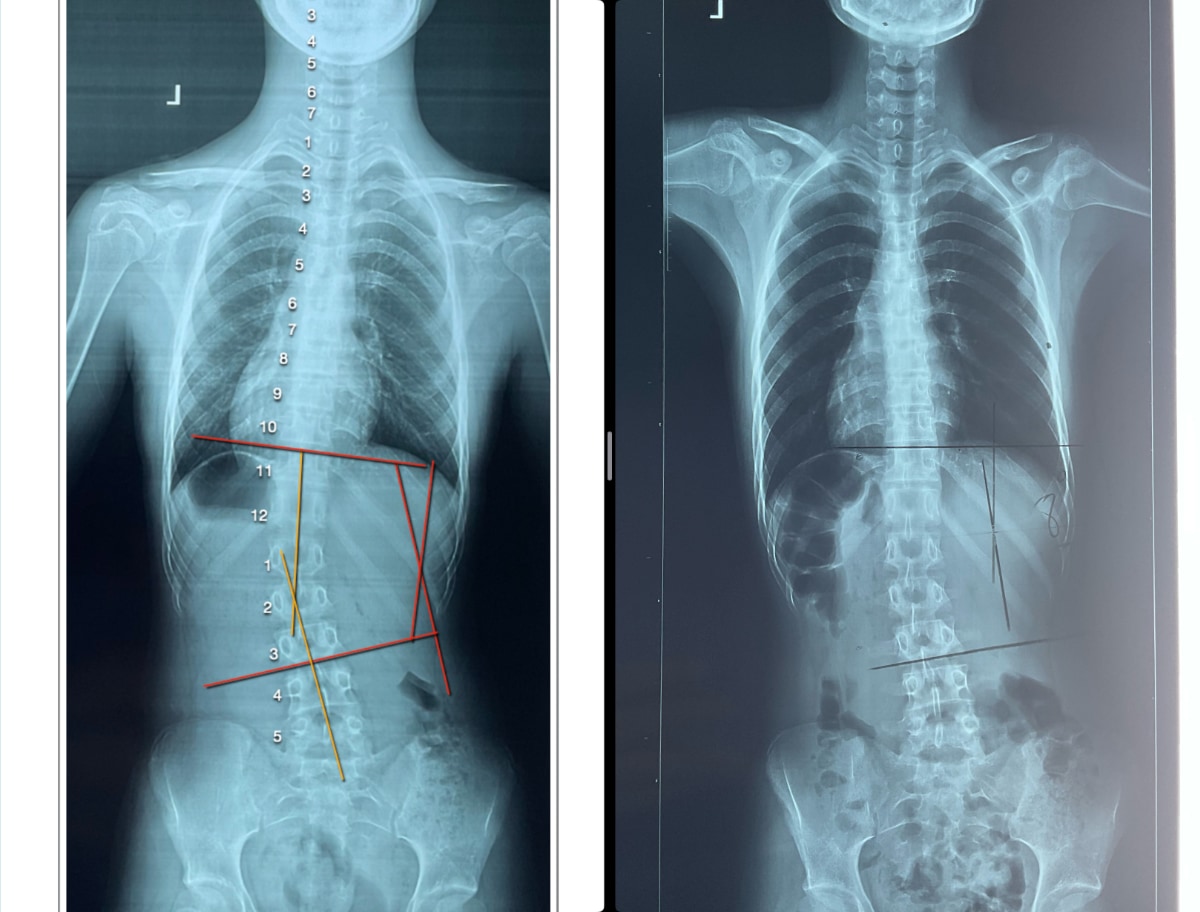

A 13-year-old girl, concerned with her 15-degree scoliosis curvature and poor posture. After completing 30 treatment sessions, remarkable results were achieved. The girl’s posture showed significant improvement, and her scoliosis curvature was reduced to just 8 degrees.